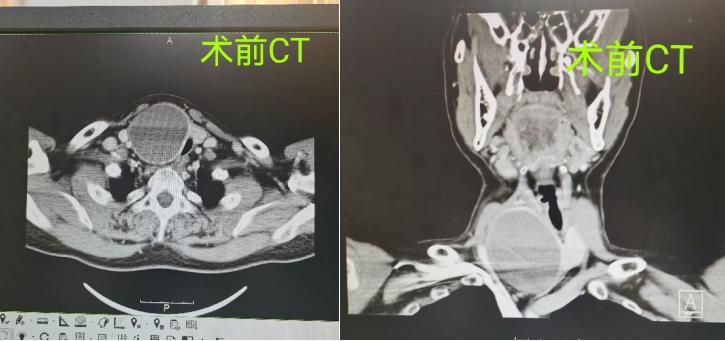

△术前CT影像

患者情况:李某,男,48岁,因呼吸及吞咽受限2月急诊入院。

2月前患者开始出现呼吸及吞咽受限且逐渐加重,同时,患者颈部逐渐增粗、隆起。在外院查颈部彩超提示甲状腺右叶囊实性结节,TI-RADS 3级。现为进一步治疗来诊,急诊拟“甲状腺肿物伴呼吸道梗阻”收入院。

专科查体:颈软,无抵抗,气管受压左偏,颈前区团状肿块隆起。右侧甲状腺区可触及一肿物,约5X4cm,质中,边界尚清,轻微压痛,随吞咽上下移动。左侧甲状腺未触及明显肿物,双侧颈部未触及肿大淋巴结。入院行结节US-FNA,未见癌。